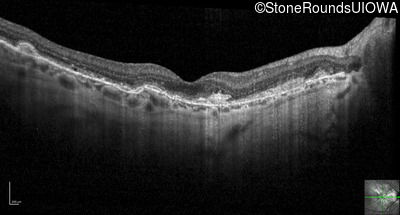

Optical Coherence Tomography - Left - 20/20 -2

Exemplar / OCT Stack

OCT Stack